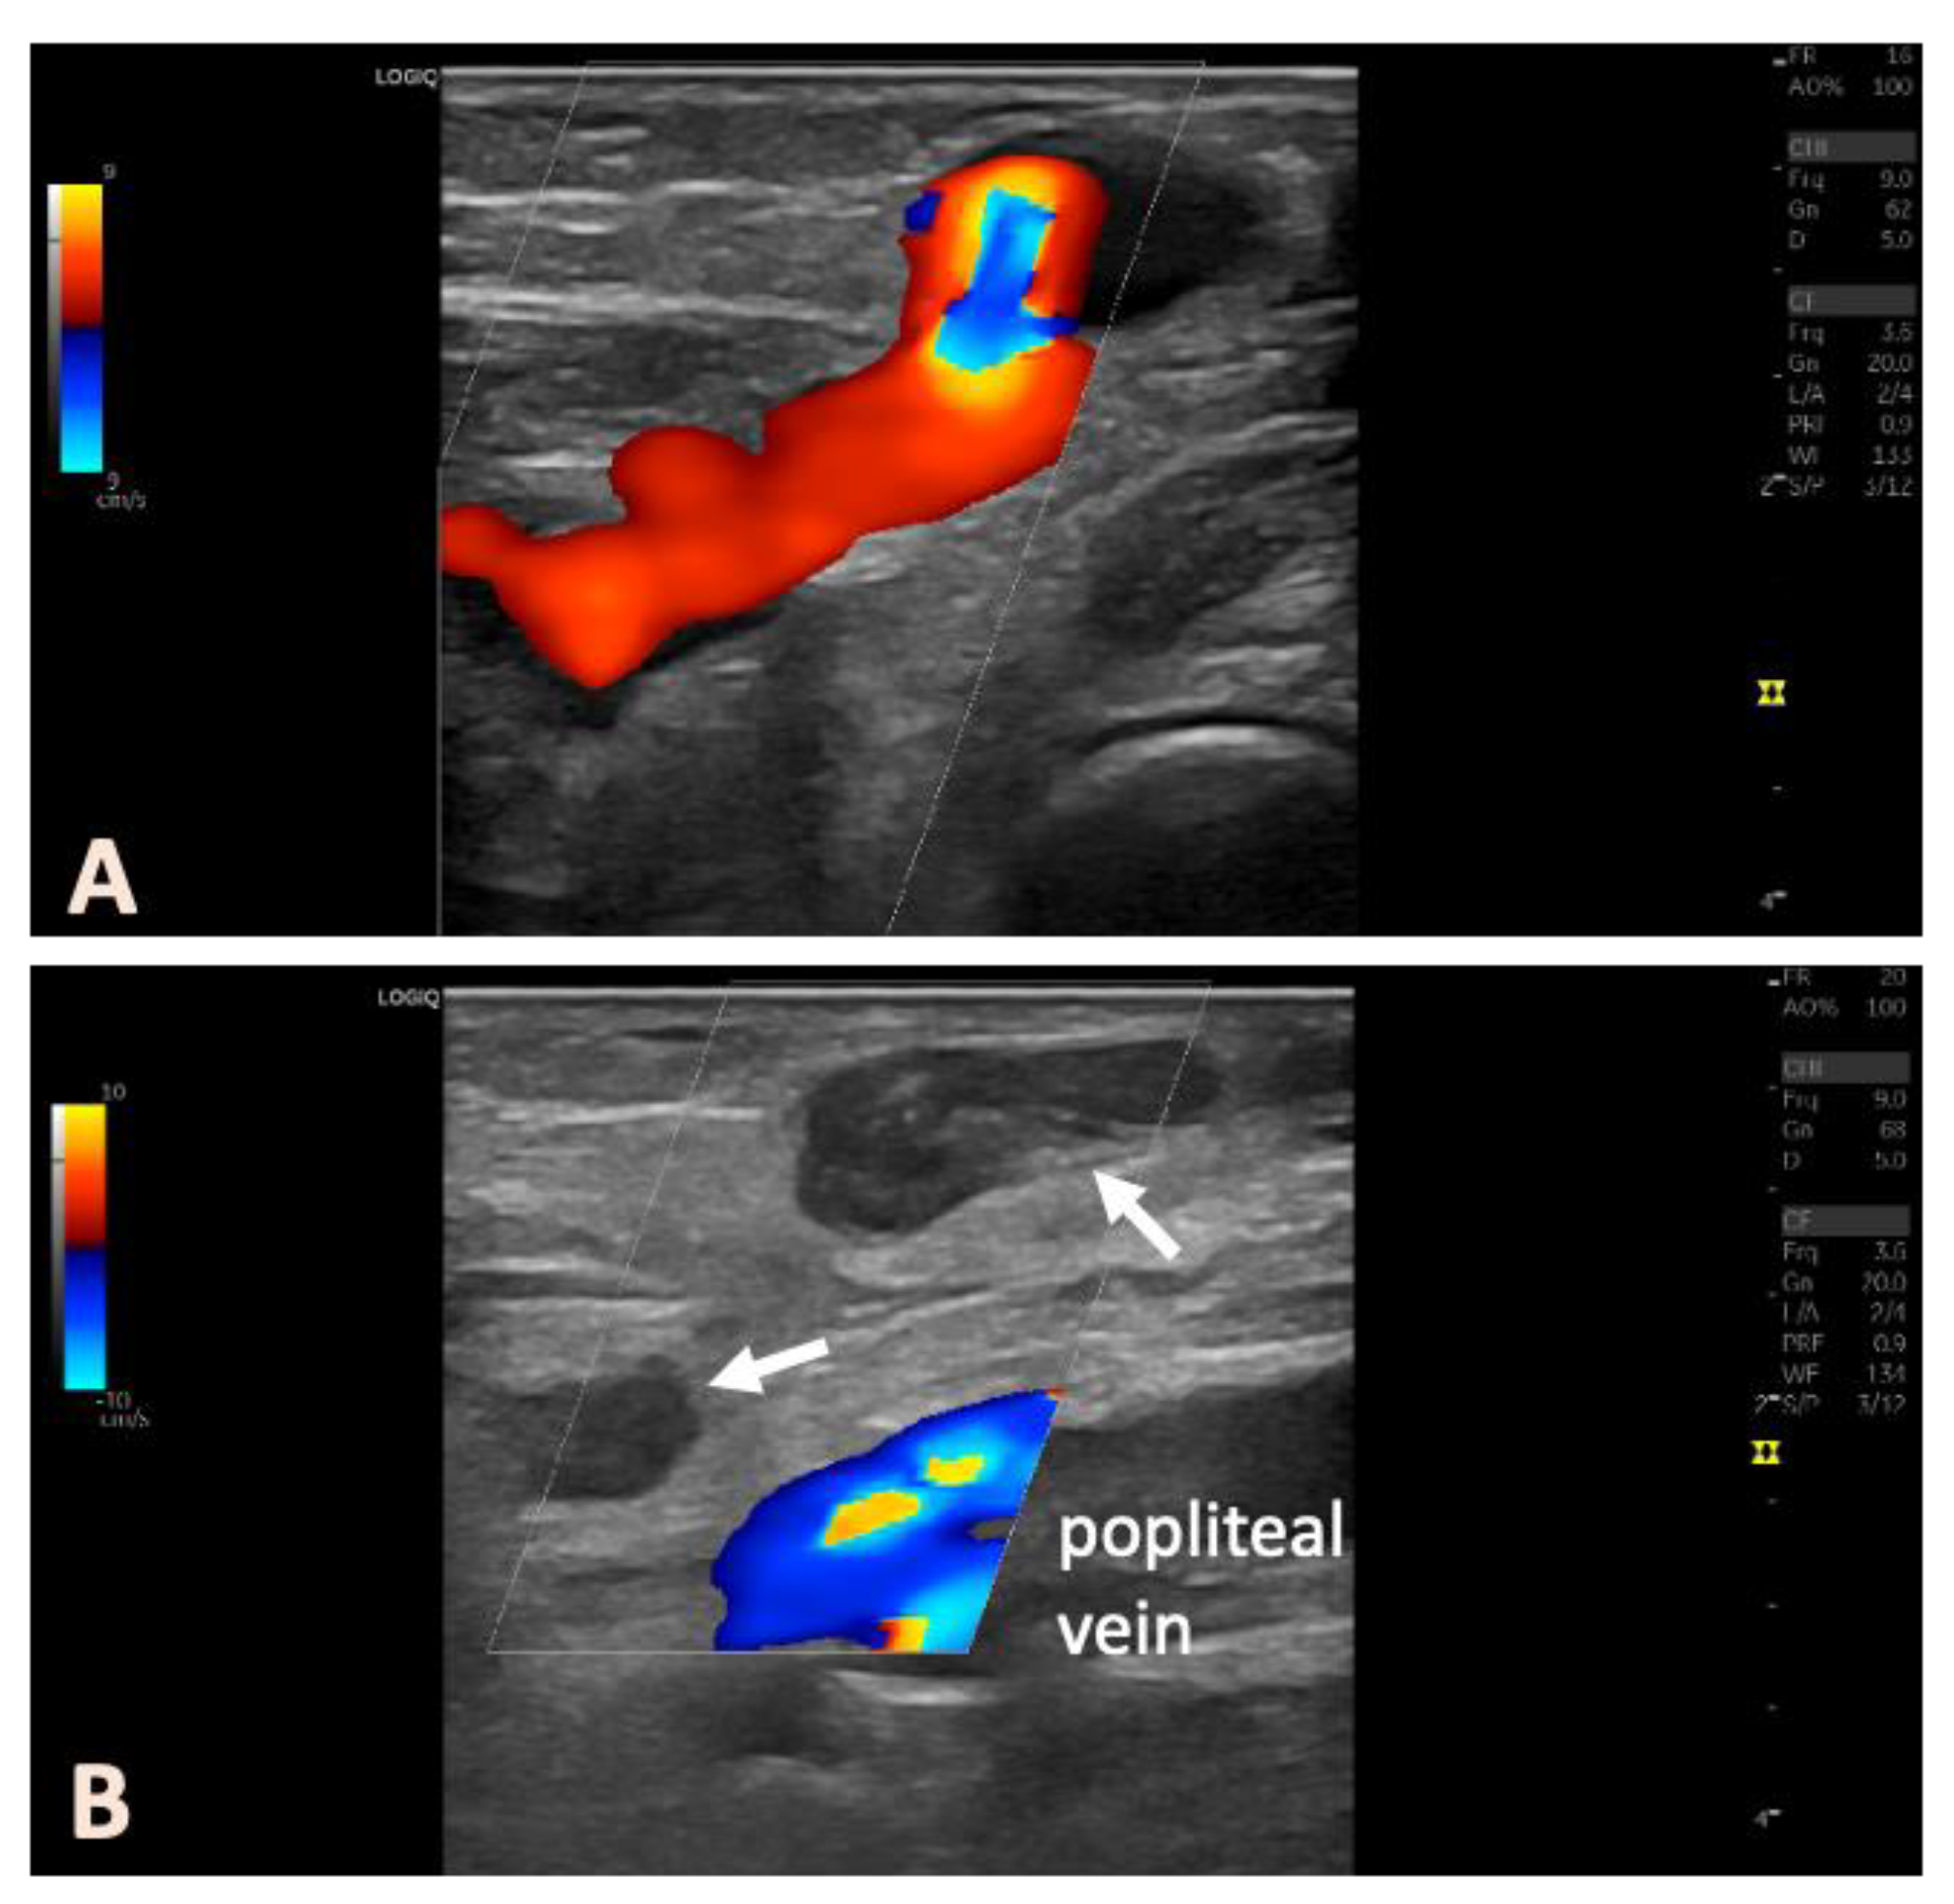

2.2. Preoperative Diagnostics

2.3. Interventional Treatment